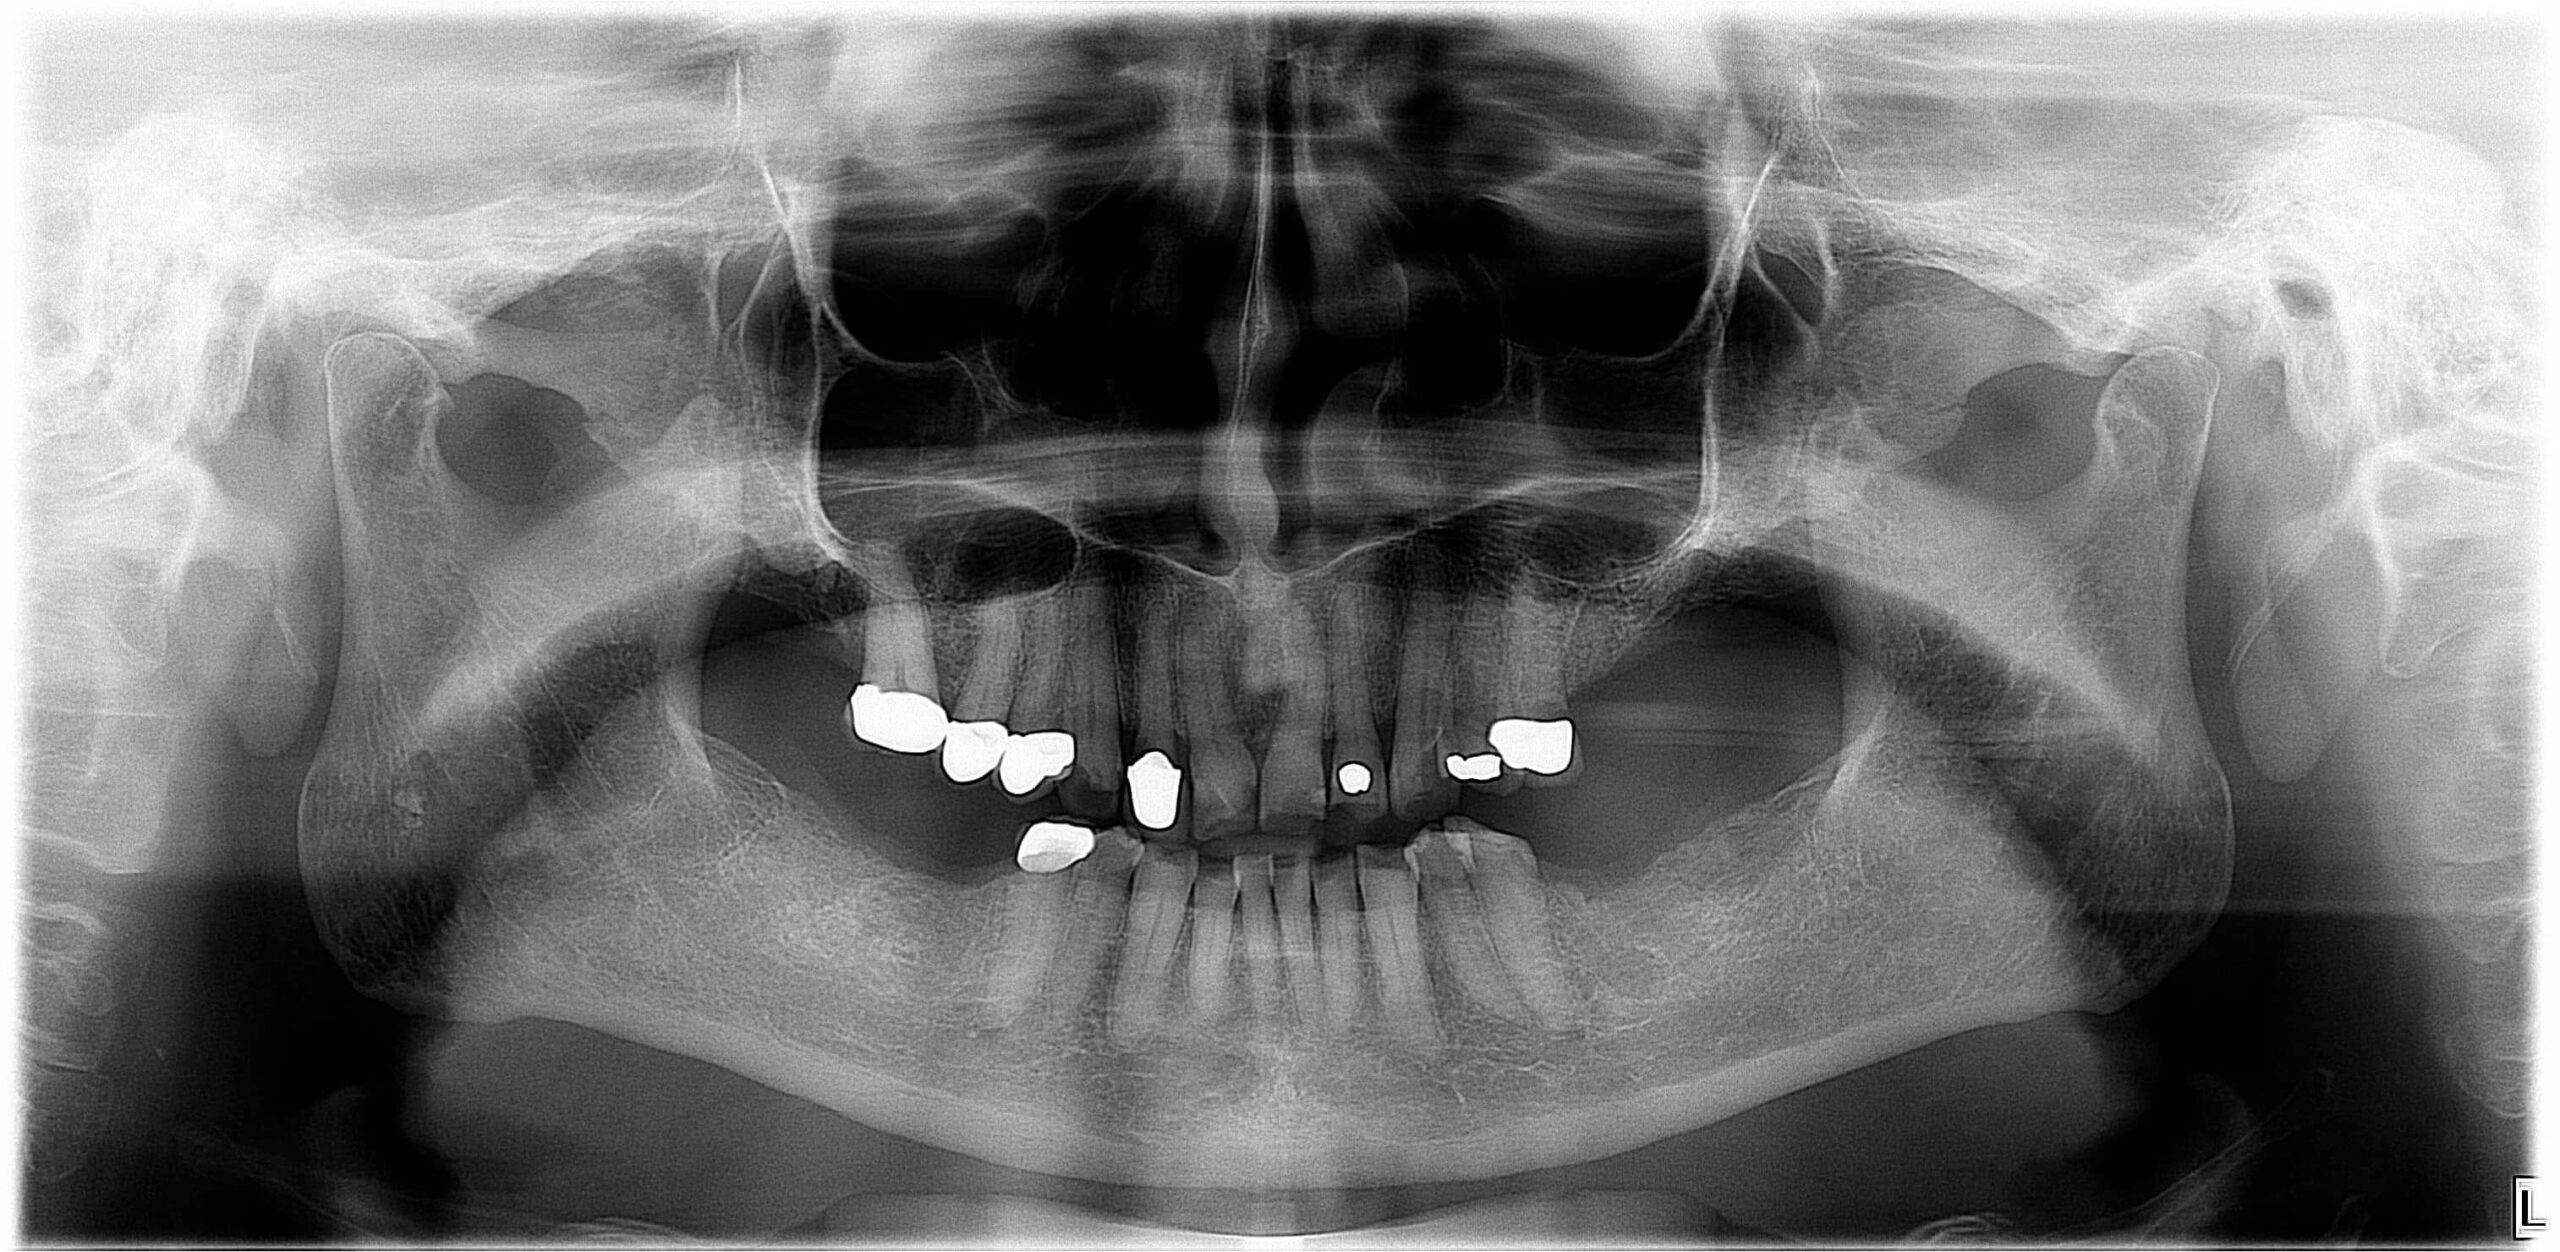

- Nem megfelelően kialakított fogpótlások: rosszul illeszkedő koronák, hidak vagy kivehető pótlások hosszú távon megváltoztathatják a harapási viszonyokat, túlterhelhetik az állkapocsízületet, és funkcionális egyensúlyzavart idézhetnek elő. Ez gyakran vezet feszüléshez, rágás közbeni fájdalomhoz vagy ízületi kattogáshoz.

Az állkapocs működésének vizsgálatával külön tudományterület foglalkozik: ezt nevezzük gnatológiának. A gnatológia a rágószerv működésének és zavarainak – így az állkapocsfájdalomnak, ízületi kattogásnak, fogcsikorgatásnak vagy harapási eltéréseknek – komplex vizsgálataira specializálódott. A gnatológiai szemlélet a fogászati diagnosztikában egyre nagyobb szerepet kap, mivel nem csupán a fogak állapotát, hanem a rágóizmok, az állkapocsízület és az okklúzió (harapási viszonyok) összhangját is vizsgálja.

Fogászati kezelés

- Fogtályog, szuvas fog, gyulladás vagy foghúzás utáni komplikáció esetén antibiotikumos kezelés, gyökérkezelés vagy sebészi beavatkozás lehet szükséges

- Bölcsességfog okozta fájdalom esetén gyakran javasolt az érintett fog eltávolítása

Gyakori, hogy az állkapocsfájdalmat nem egyetlen ok, hanem több együttes tényező váltja ki. A gnatológiai vizsgálat ilyenkor segíthet feltárni a harapási eltéréseket, az állkapocs eltolódásainak vagy az ízület túlterhelésének hátterét. A gnatológiai diagnosztika során különféle funkcionális tesztek, rágóizom-analízis, artikulációs vizsgálatok és állkapocsmozgás-elemzés történik, amelynek alapján a kezelési terv sokkal célzottabbá válik.